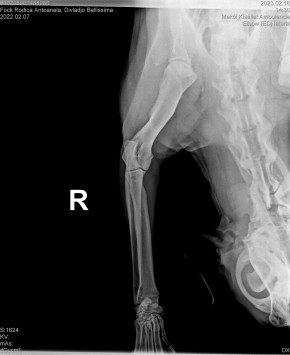

DIVLADJO BELLISSIMA

( BELLISSIMA )

Data nasterii:

07.02.2022